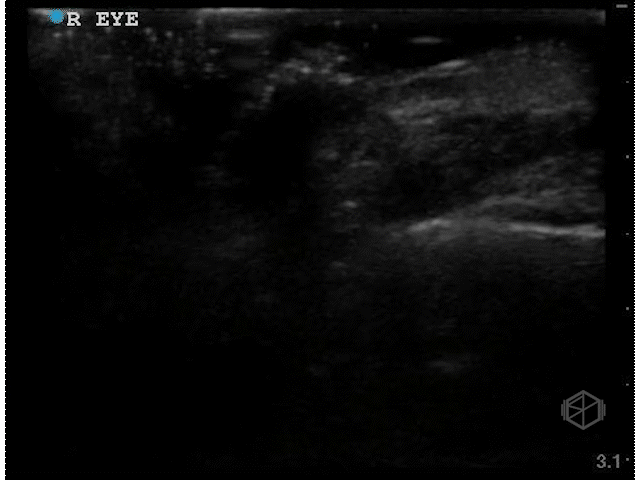

Dr. Singh scanned a ~40-year-old male with a past medical history of diabetes, hypertension, and substance abuse with diminished vision for 3 weeks.

These clips are good — there is a scan both ways through the eyes in transverse and sagittal orientations. There appears to be something irregular the posterior aspect of the vitreous, however there is not enough detail.

Dr. Singh appropriately did the next step — he increased the gain significantly and performed oculo-kinetics (have the patient move their eye rapidly).

The above clips demonstrate some interesting pathology. There appears to be a hyperechoic flap tethered to the optic nerve. This patient has a retinal detachment. There may also potentially be a vitreous detachment.

• Retinal detachment appears as a thick hyperechoic membrane. It can be tethered to the optic nerve if large, or if smaller (or not close to to the optic nerve), attached to another portion of the posterior wall of the eye. The retinal detachment will move slightly with oculo-kinetics but will remained tethered. POCUS has a high sensitivity and specificity if done correctly for the detection of retinal detachments.

• It is important to scan the eye in multiple planes to detect retinal detachments.